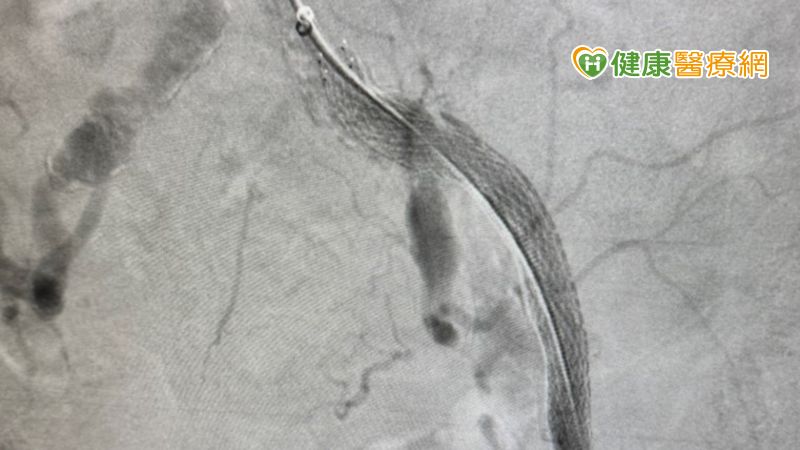

▲朱新凱醫師表示,目前使用塗藥支架是嚴重周邊動脈阻塞患者,術後再阻塞(再狹窄)率最低的手術方式之一,若經濟許可,患者能以差額負擔的方式使用此手術。

▲朱新凱醫師表示,臨床上很常可以看到同一條血管多段堵塞的患者,醫師會評估最適合患者的治療方式(圖為使用支架放置術撐開血管)。

朱醫師表示,使用傳統血管繞道手術治療周邊動脈阻塞,手術一年後的再阻塞(再狹窄)率約有50%;使用健保給付的塗藥氣球或裸金屬支架,則約為25%-30%;而若是選擇使用最新的塗藥支架,數據顯示則只有13%的再阻塞率,相比前面兩項治療方式低上不少。朱醫師說明,沒有病患在放置支架後,會想要再進行第二次手術處理血管阻塞,若是病患經濟許可,目前治療嚴重周邊動脈阻塞的首選是使用塗藥支架。最新的報告也指出,過去醫師們曾擔心塗藥支架的血栓問題,在經過大規模長期的臨床試驗後,也已經證實塗藥支架與裸金屬支並無死亡率上的差異,患者若依照醫師指示,配合正確的術後藥物及生活習慣調整,塗藥支架能為病患帶來較低的再阻塞風險。